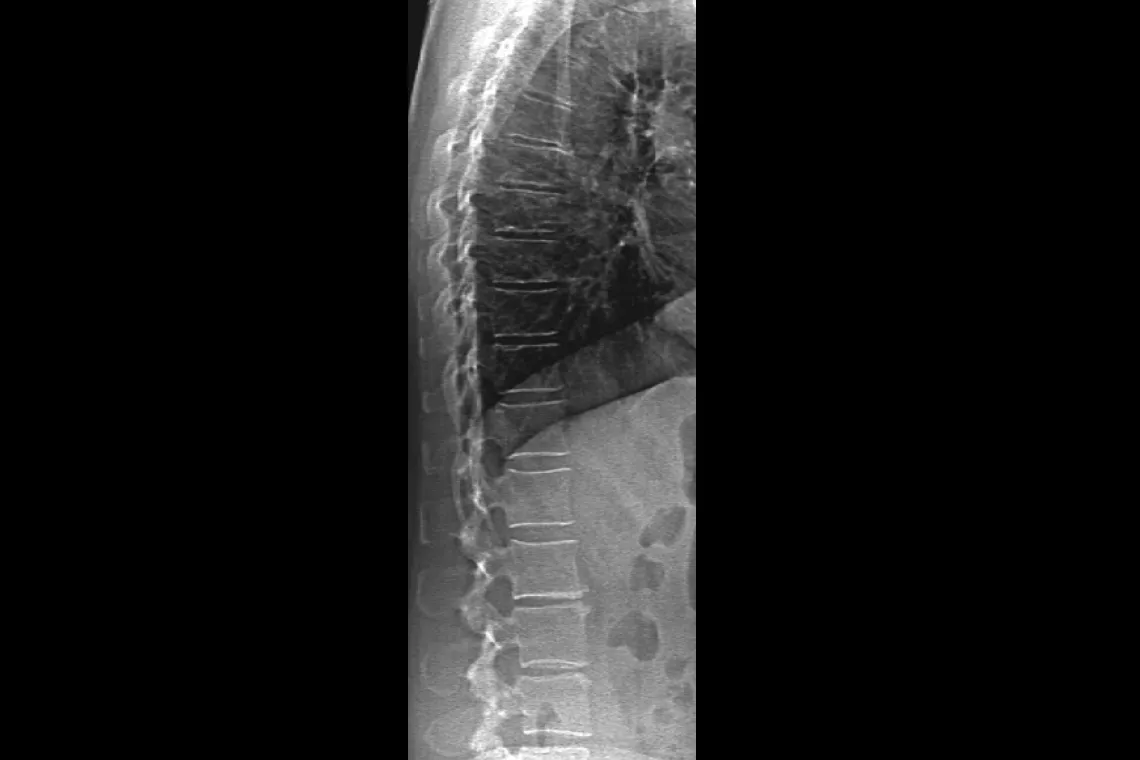

Horizon DXA produces radiographic quality images of the entire femur for assessment of potential atypical femur fractures.31 A quick, 15-second scan reveals cortical thickening of the bone, making it fast and easy to monitor the effects of bisphosphonate therapy over time.

Assess fracture risk by combining an accurate measurement of bone density with high-resolution vertebral imaging. You can identify spine fractures with a low-dose, single-energy image in 10 seconds.

Improve accuracy and reduce post-exam analysis errors with precise, software-assisted placement of inter-vertebral disc spaces for graphic analysis.

A new digital high-resolution ceramic detector array is paired with true fan-beam acquisition geometry to enable rapid, dual-energy bone density measurements in a single-sweep scan. OnePass eliminates beam overlap errors and image distortion found in rectilinear acquisition techniques — for superior image quality and data stability. Another Hologic exclusive.